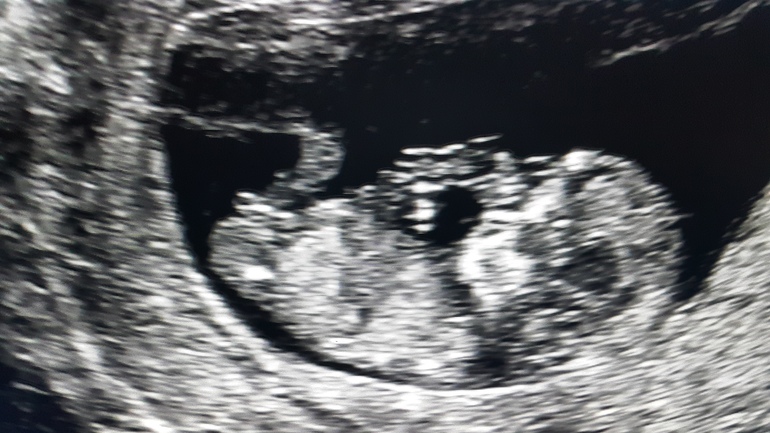

Вчера была на 1м скриниге.

Вот такой малышок. Ножек на снимке не видно, но мне показали, они длинные.